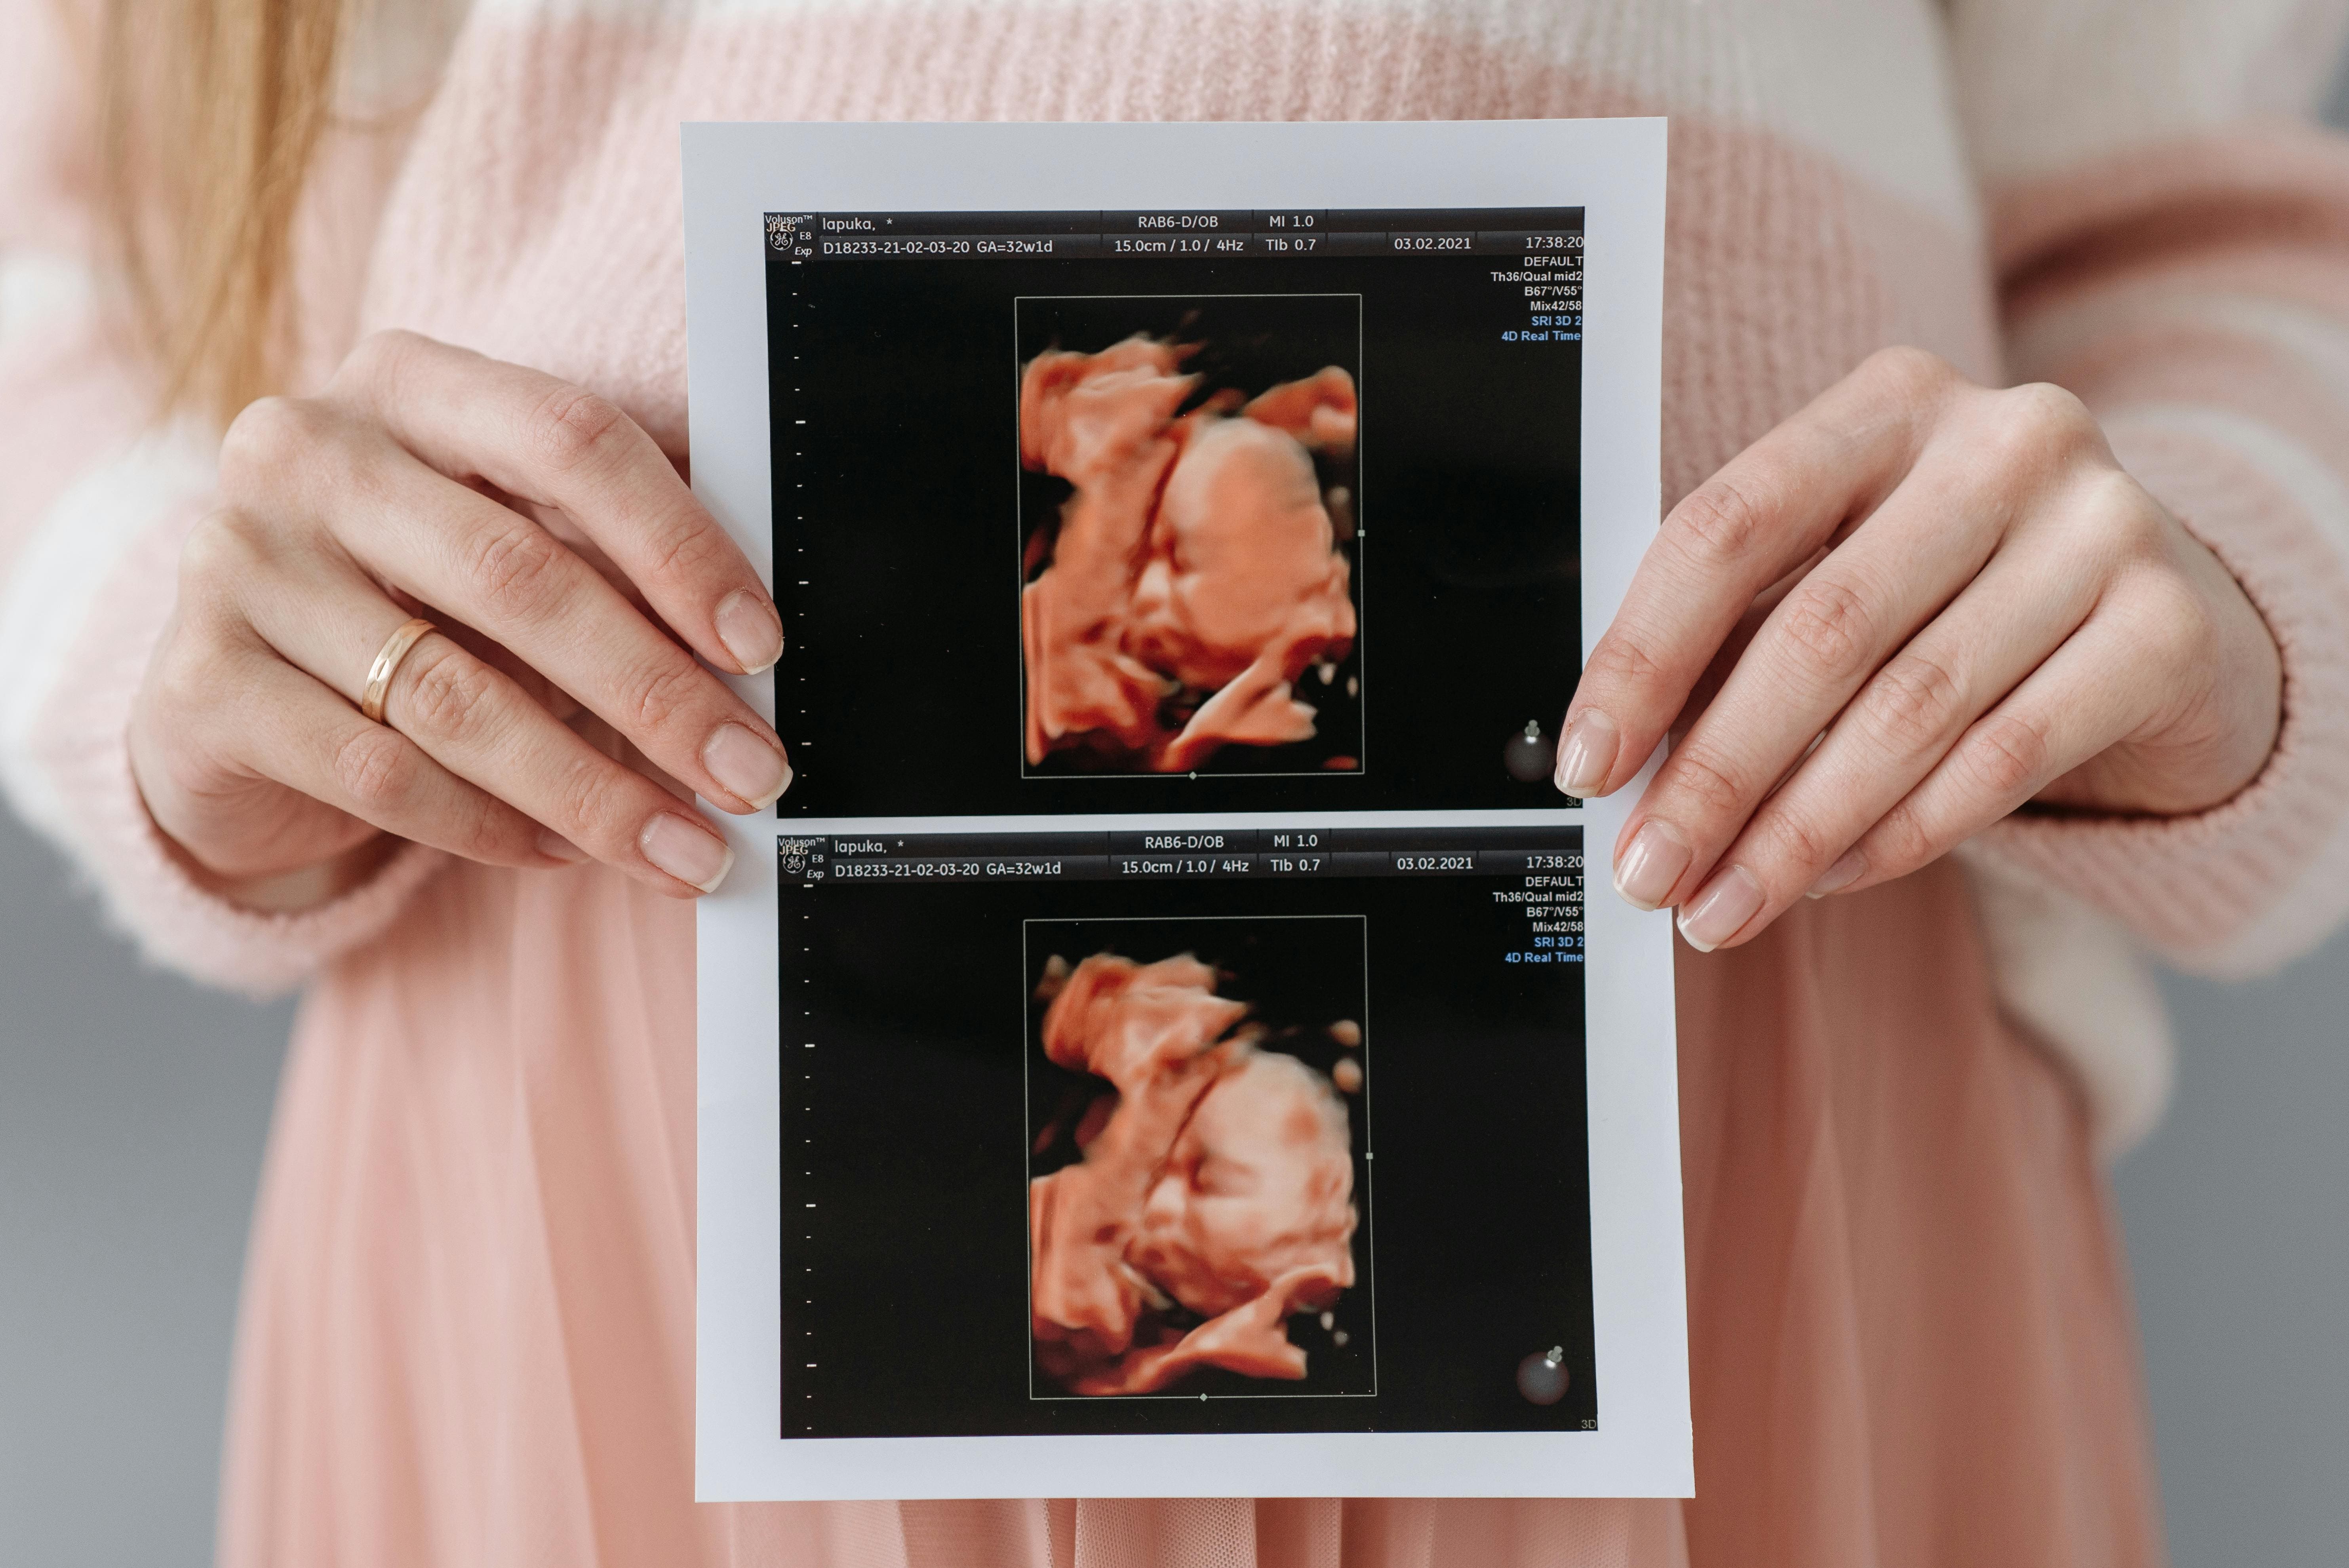

임신 기간 동안 많은 설렘과 기대를 느끼지만, 출산 진통에 대한 두려움도 함께 커지고 있으신가요? 😰 특히 첫 아이를 갖는 예비 엄마라면 이러한 걱정이 더 크실 거예요. 많은 산모들이 무통분만으로 통증을 줄이며 출산하고 있어요. 오늘은 출산을 앞둔 예비맘들을 위해 2025년 최신 무통분만 정보를 알아볼게요!

무통분만은 통증을 완전히 없애는 것이 아니라, 크게 줄여주는 방법이에요. 경막 외 마취가 가장 일반적이며, 산모와 아기 모두에게 안전한 것으로 입증되었습니다. 2025년 현재 초산모의 94% 이상이 선택할 정도로 보편화되었어요.

2025년 현재 무통분만, 특히 경막외 마취는 초산모의 94% 이상이 선택할 정도로 인기가 많아요. 이렇게 많은 산모들이 선택하는 이유, 즉 장점을 알아볼게요.

특히 고혈압, 당뇨, 임신중독증 등 고위험 임신이나 쌍둥이 출산의 경우 무통분만이 큰 도움이 될 수 있어요. 심한 통증으로 인한 스트레스 호르몬이 이런 상태를 악화시킬 수 있기 때문이에요.